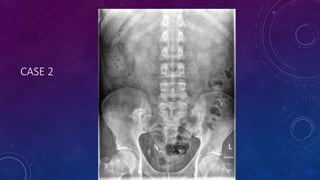

CASE 2

• Failed kidney transplant

• Seminal vesicle / vas deferens calcification